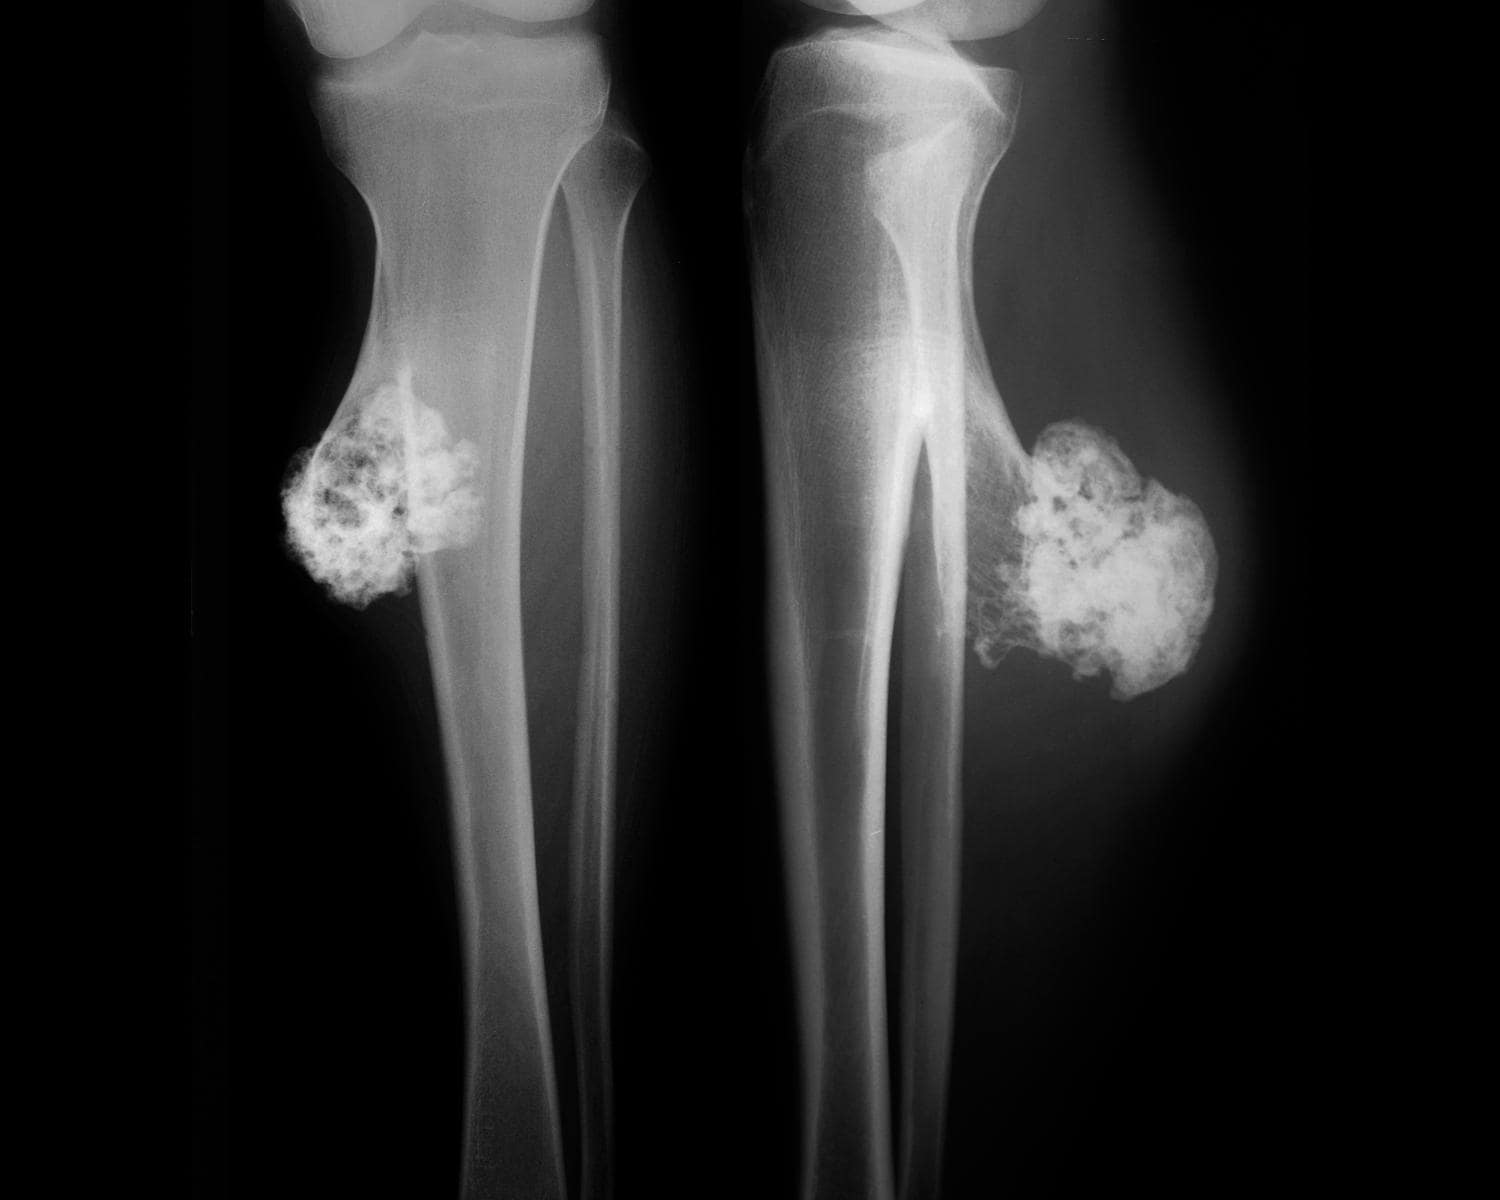

L’osteocondroma (o esostosi osteocartilaginea) è un tumore osseo benigno particolarmente frequente che, pur potendo avere origine da qualunque tipologia di osso, tende a presentarsi maggiormente in corrispondenza delle estremità delle ossa lunghe (porzione distale del femore, porzione prossimale di tibia e omero o attorno al ginocchio); interessa principalmente i pazienti giovani (di sesso maschile e di età compresa tra i 10 e i 20 anni) e solo raramente, in età adulta, può trasformarsi in una tumorale maligna, nota come “condrosarcoma”.

L’osteocondroma si presenta come una lesione solida che ha origine da una porzione di cartilagine (tessuto connettivo che riveste la superficie delle ossa, garantendo maggiore resistenza e funzionalità all’apparato locomotore) e che si espande progressivamente all’interno del tessuto osseo; in molti casi tende a localizzarsi in corrispondenza dell’estremità delle ossa lunghe, dove può aumentare di volume durante il periodo dell’accrescimento, senza dar luogo a particolari sintomi oppure causando dolore (specialmente durante il movimento articolare).

In altri pazienti, invece, questo tumore si inserisce nell’ambito di una patologia nota come “esostosi multipla ereditaria”, un disordine di natura genetica in cui si assiste alla crescita di osteocondromi multipli, localizzati in corrispondenza delle estremità di diverse ossa lunghe o a livello delle ossa piatte (bacino, scapola); in questo caso la malattia riconosce una trasmissione autosomica dominante, per cui il figlio di un individuo ammalato, avrà il 50% di possibilità di contrarre a sua volta questa patologia.

Successivamente, per confermare la diagnosi, è necessario eseguire un esame radiografico della regione anatomica interessata e, qualora si sospetti un processo di degenerazione maligna della neoplasia, una biopsia ossea (esame di laboratorio condotto su un campione di tessuto osseo ricavato attraverso agobiopsia o tramite biopsia ossea “a cielo aperto”).